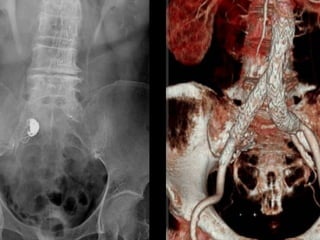

Female 77yo

Pulsating Abdominal Mass

80 yo male

Asymptomatic A-I Aneurysm